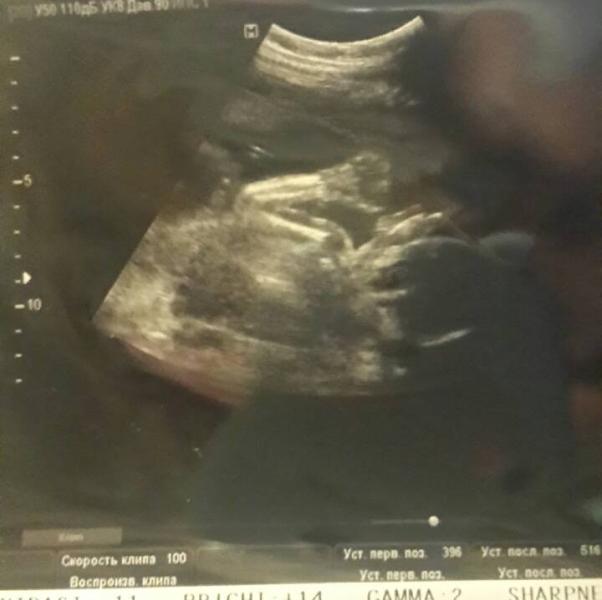

Ну вот мы с мужем сходили на второй скрининг:) сказать что он в восторге, это не сказать ни чего😉 ручкой маме с папой помахал🙋 по размерам опять больше на неделю, это же не страшно? у кого так было? врач сказала, что либо рожу раньше, либо крупный плод😕